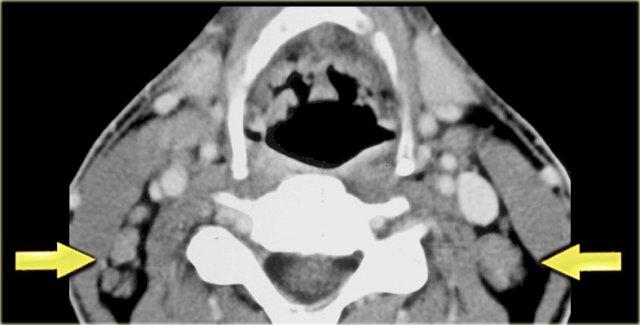

Bên trái là hình CT ở mức sụn giáp.

Có một khối không đều nằm trung tâm ở xoang lê bên phải.

Khối này nằm trong khoang tạng.

Ở vùng này, khối u thường gặp nhất là ung thư biểu mô tế bào vảy.

Chẩn đoán này đã được xác nhận qua sinh thiết.

Lưu ý khoang sau hầu (mũi tên vàng).

Đây là khoang ảo chỉ chứa một ít mô mỡ.